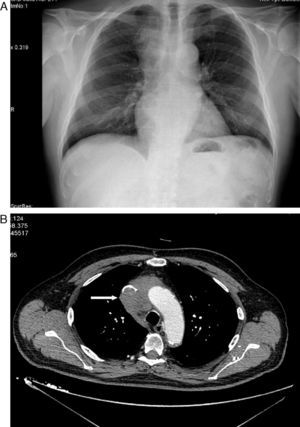

Varón de 71 años hipertenso, dislipémico, con antecedentes de fibrilación auricular, anticoagulado y con cardiopatía isquémica estable. Consultó en el servicio de urgencias por inflamación en cara, cuello y hombros de 15 días de evolución sin síndrome constitucional ni clínica respiratoria previa. En el examen físico presentaba presión arterial de 139/81mmHg, 62 latidos/min y auscultación cardiopulmonar normal. Destacaba el edema en tórax superior, cuello y cara. En la radiología de tórax se objetivó una masa mediastínica superior derecha (fig. 1A), por lo que se realizó una tomografía computarizada (TC) torácica que informó de una masa en mediastino superior derecho que infiltraba y ocluía la VCS (fig. 1B) y pequeñas adenopatías paratraqueales inferiores e hiliar derecha. El hemograma mostró ligera leucocitosis de 10.400/uL. La bioquímica, la coagulación y los marcadores tumorales (alfa-fetoproteína, PSA, CEA, Ca. 19.9 y β2 microglobulina) fueron rigurosamente normales. Se realizó TC abdominopélvica, que descartó alteraciones en otros territorios. Se inició tratamiento con dexametasona, con gran mejoría clínica del paciente, y se procedió a la biopsia guiada por TC, que fue informada como carcinoma tímico. Según el sistema de estadificación de Masaoka se trataba de un estadio III-IVb (invasión microscópica de órganos vecinos [VCS en este caso] y metástasis linfáticas paratraqueales inferiores e hiliar derecha). El paciente fue dado de alta con corticoides y continuó el tratamiento quimioterápico con carboplatino y etopósido. Posteriormente recibió, sin éxito, radioterapia para intentar disminuir la masa tumoral y conseguir la resecabilidad quirúrgica de la misma.